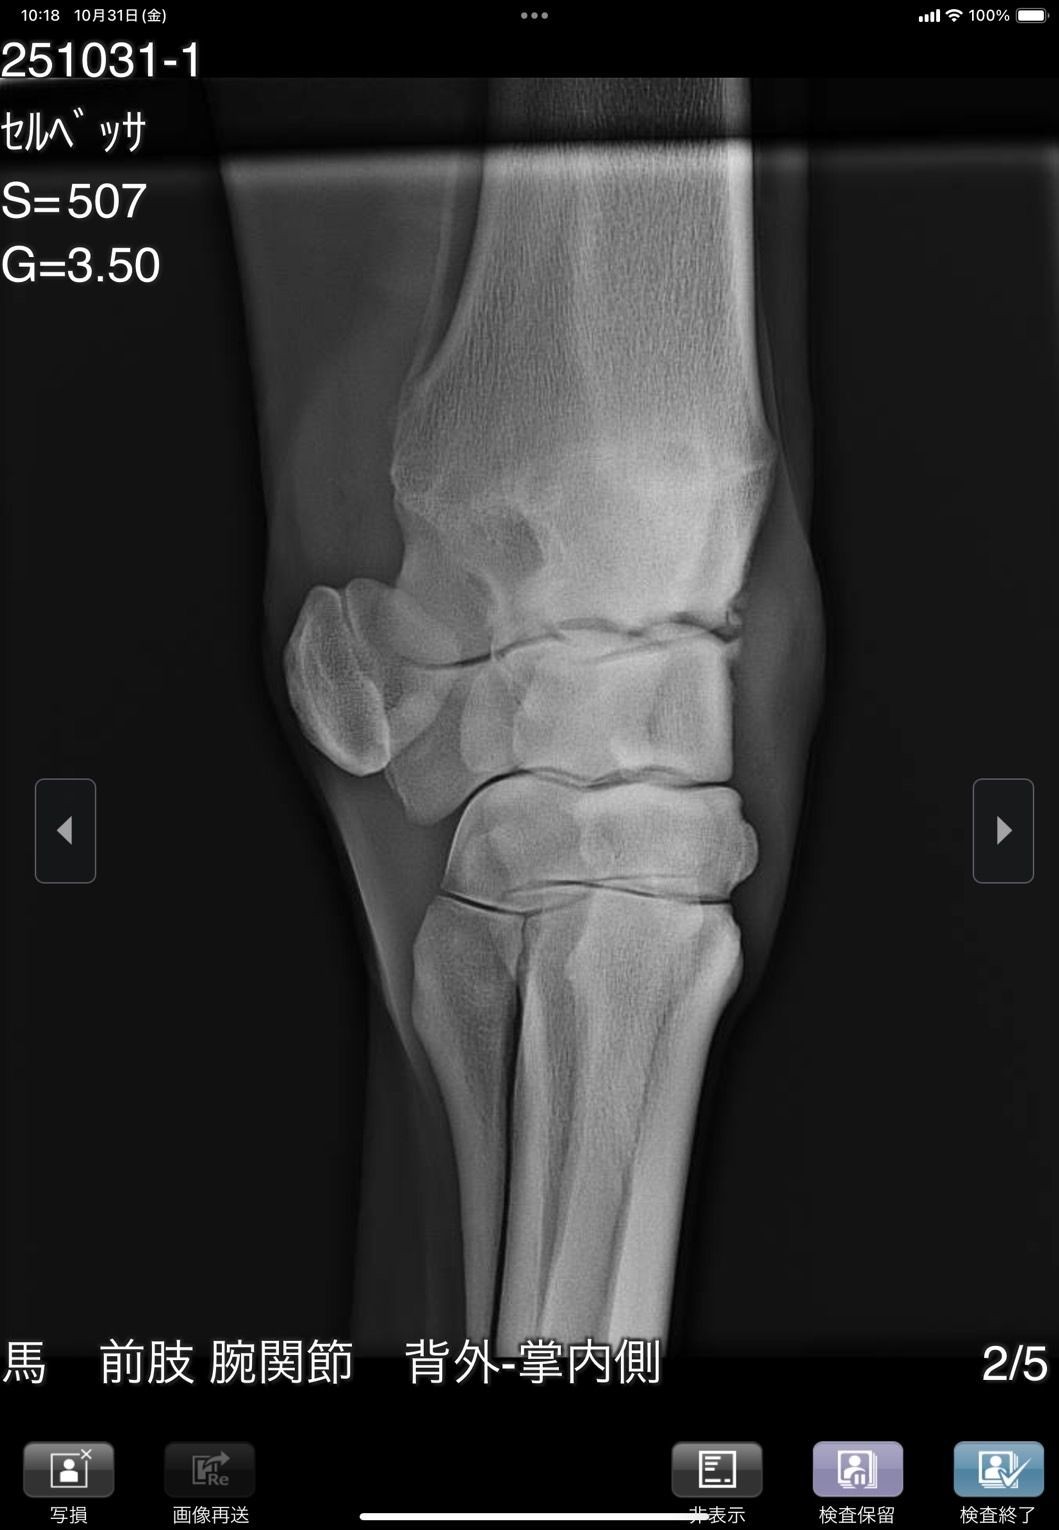

前肢が外向しているためか1歳秋の育成段階で右前に骨瘤ができ、中々固まらずに育成も遅れ、デビューは3歳4月となりました。デビュー後は4ヶ月で6戦を消化し比較的順調に出走できましたが、8/28の出走後にC3級への降級を狙って休養へ。帰厩に向けて乗りこんでいる所でしたが、10/31の調教後に右前膝に違和感があり、レントゲン検査を実施した所、骨片の剥離が見られました。その段階では大きな跛行は見られなかったためしばらく様子を見ましたが、速い調教を行うと歩様に違和感が出るため、手術が必要と考えられます。骨片除去手術を行いますと一定期間の休養が必要となるため、この度オークションへの出品とさせて頂きました。骨片除去手術は必要になると思いますが、元々の戦績からすると園田C2級で勝ち負け出来る能力があり、休養中にC3級への降級となりますので、適切な治療と休養をして頂ければ勝負になる可能性は高いと思います。骨折の状況については8/31撮影のレントゲン画像をご確認ください。

※10月31日の調教後に右前膝に違和感があり、レントゲン検査を行った所、骨片の剥離が見られました。